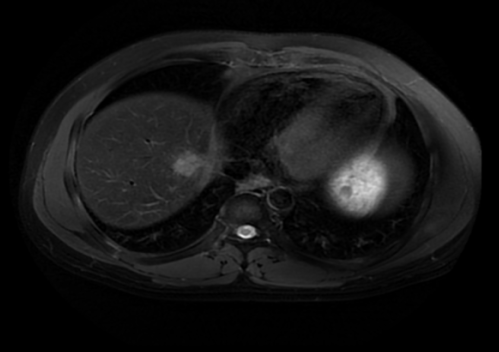

2022.05.08化疗两周期后复查肝脏MRI:肝VIII段低密度影,大小约2.3cm×1.9cm

2022.09.21肝脏放疗结束后复查肝脏MRI:肝VIII段转移灶治疗后改变,病灶基本消失。

2023.01.14定期复查肝脏MRI:肝VIII段转移灶治疗后改变,未见复发征象。

2023. 04.26复查肝脏MRI:肝VIII段转移灶治疗后改变,未见复发征象。

“医生们定期进行肝脏磁共振检查,结果显示肿瘤逐渐缩小,如同拨云见日。”邱素芳主任介绍,鼻咽癌治疗一定要边观察边调整,根据病人的实际情况和疗效来调整治疗方案及强度、在综合治疗的同时,又要具有个体化特点。